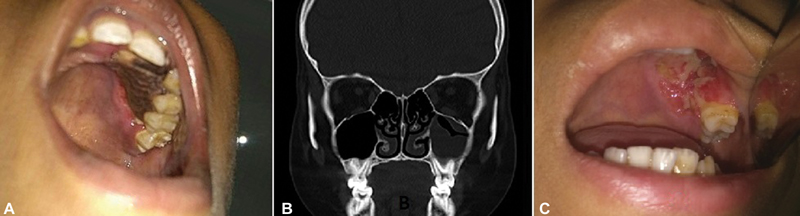

A 12-year-old child, who had completed the dexamethasone-based induction phase of chemotherapy for Near Early T cell precursor acute lymphoblastic leukemia (ETP-ALL), was admitted to the high dependency unit of pediatric hemato-oncology with febrile neutropenia. The child was on fluconazole for?Candida tropicalis?septicemia when he developed a blackish crust on the left side upper alveolus and adjacent hard palate. While the otorhinolaryngology team was called for further evaluation of this new symptom, the patient was started on conventional amphotericin B with the starting dose of 0.5?mg/kg/day, which was increased to 1.5?mg/kg/day after 2 days. On enquiring further, there were no associated complaints of nasal discharge, blockage, postnasal drip, or any ear or throat complaints. General examination revealed that the boy was febrile and had tachycardia. On local examination, there was a black eschar of 3?cm???2?cm along the left maxillary alveolus extending to the adjacent hard palate, as shown in [Fig. 1A]. The lesion had involved the canine and the first two left maxillary premolars, with a visible oroantral fistula along the labial surface of the alveolus. Potassium hydroxide (KOH) mount from the scrapings of the lesion revealed filamentous fungal elements in the form of broad, sparsely septate hyphae, branching at 90?degrees, suggestive of mucormycosis. Blood counts showed severe neutropenia with thrombocytopenia. Computed tomography of the paranasal sinuses, depicted in [Fig. 1B], showed mucosal thickening in the ipsilateral maxillary sinus, without any bone erosion. The patient was taken up for emergency surgical debridement via a transoral approach, with adequate platelet transfusions and reserve. Intraoperatively, the debridement of dead bone accompanied the removal of the left upper canine, premolar, and first molar for disease clearance. On-table examination of the mucosa of the left maxillary sinus was found to be not involved except on the floor, adjacent to the diseased alveolus. Following the surgical debridement, the patient continued to receive conventional amphotericin B for 28 days, during which he developed intermittent but marked electrolyte disturbance, requiring daily potassium and magnesium corrections. He was also started on interim 6 mercaptopurine within 48?hours of surgery, for a duration of 14 days, following which the consolidation chemotherapy was continued. The last week of therapy with amphotericin B was overlapped with tablet posaconazole, at the dose of 300?mg twice daily on the first day and 300?mg once a day thereafter. The patient was discharged on tablet posaconazole, which he took until the end of the intensive phase of chemotherapy that lasted nearly 5 months. As demonstrated in [Fig. 1C], the palatal wound healed well without any evidence of recurrence on three subsequent follow-up visits 1 month apart. The nasogastric tube was removed in the second month of surgery, and the oral feeds were started successfully without nasal regurgitation. Currently, the patient is in remission and free of fungal disease, and awaiting prosthodontic rehabilitation for missing teeth.

|?Fig. 1? Clinico-radiological images of case-1, showing necrosis of left hard palate adjacent to premolar teeth in A, the coronal image of computed tomography with minimal mucosal thickening in B, and healed surgical defect after a month of debridement in C.|